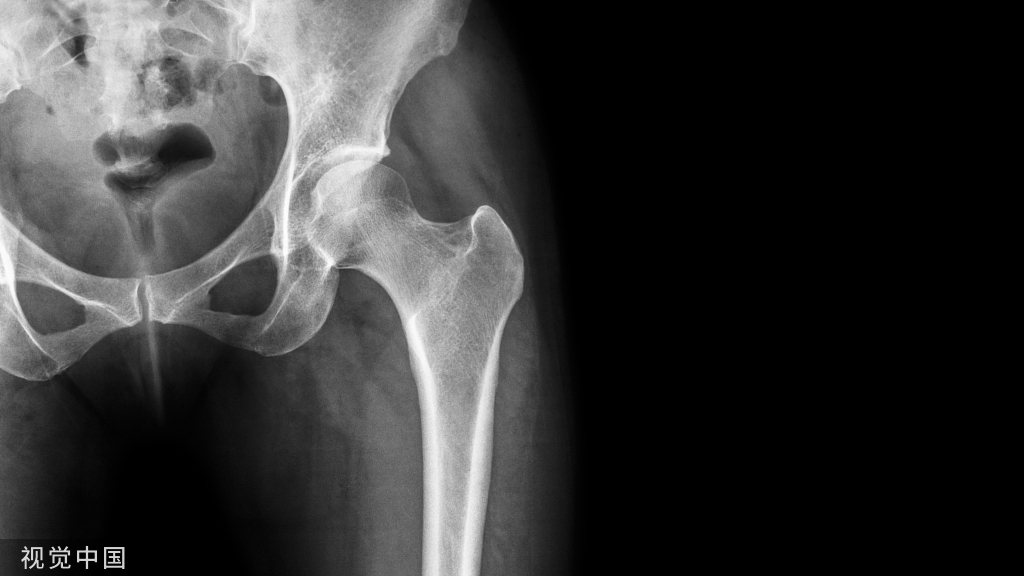

髋关节退行性骨关节病

又称髋关节骨性关节炎,是以髋关节软骨退变和其边缘骨质增生为特征的非炎症性疾病,可继发于其它疾病。

病理:髋关节软骨的退行性变,尤以承重部为著。关节软骨逐渐消失,骨端部硬化、骨赘形成,骨质疏松,关节面囊性变,晚期关节内游离体,关节间隙狭窄。

临床表现:多在50岁后,女性多于男性,起病隐匿,缓慢渐进性发展,关节痛疼,承重时酸胀加重,休息后缓解。

影像诊断:1、X线:早期髋臼上缘密度增高,股骨头凹边缘微小骨赘形成,继续发展可见较大骨赘,关节间隙上外侧非对称性狭窄,关节面边缘骨质增厚、关节面下假囊肿形成,重者出现股骨头半脱位,关节一般无骨质疏松,软组织无明显萎缩。(首选检查)

2、CT:髋臼前后唇、股骨头及髋臼窝边缘骨质增生,骨性关节面不规则硬化,关节间隙狭窄,承重面下出现假囊肿,关节腔可见积液及游离体。

3、MRI:早期软骨内显示条状或不规则低信号带,软骨局部变薄,表面不光整;继而外缘出现骨质增生,关节面软骨下出现骨硬化带;进一步发展出现软骨下假囊肿,关节腔游离体,关节腔狭窄,甚或半脱位。